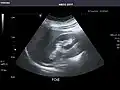

Abdominal Ultrasound (Full Exam)

STRUCTURED REPORT

(Technique: Transabdominal ultrasonography; Device: Toshiba Aplio XG)

Liver: Diffusely homogeneous and normal in echogenicity. No focal mass or contour nodularity. No intrahepatic biliary ductal dilatation.

Portal Vein: Patent main portal vein.

Gallbladder: No stones, wall thickening, or pericholecystic fluid.

Common Bile Duct: Nondilated measuring 1.3 mm at the level of the porta hepatis.

Pancreas: Visualized portions unremarkable.

Spleen: Normal in size.

Kidneys: Right and left kidneys measure 11.5 cm and 12 cm in length respectively. No hydronephrosis. Small left lower pole kidney cyst.

Ascites: None.

Aorta: Visualized portions normal in caliber, 16 x 15 mm.

IVC: Normal.

IMPRESSION:

Normal abdominal ultrasound.